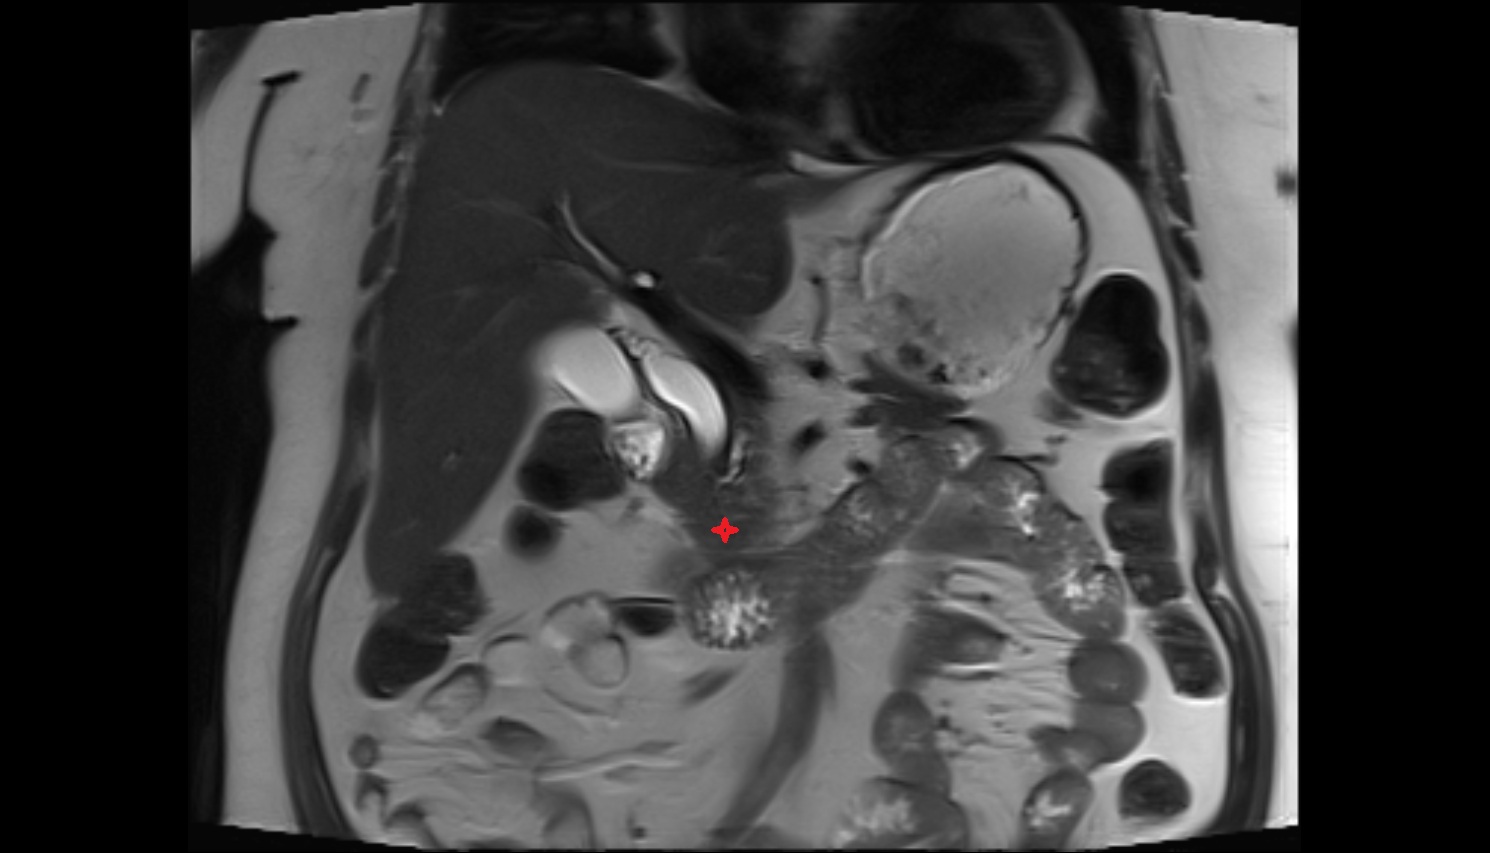

- kidneys

- Right kidney

- Left kidney

- Kidney cortex (Renal cortex)

- Renal medulla

- Renal pyramids

- Renal pelvis

- Left renal artery

- Right renal artery

- Neck of pancreas

- Head of pancreas

- Uncinate process of pancreas

- Body of pancreas

- Tail of pancreas